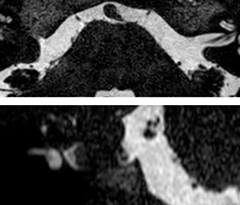

The 3D TSE T1w black blood MSDE sequence with fat suppression has an isotropic 0.8 mm voxel size and sagittal oblique and axial reformats are made. The images show superficial temporal artery thickening and peri-arterial fat infiltration. The 3D TSE PDw black blood MSDE with fat suppression has 0.55 mm isotropic voxels. The images shows focal involvement of the frontal branch of the superficial temporal artery.